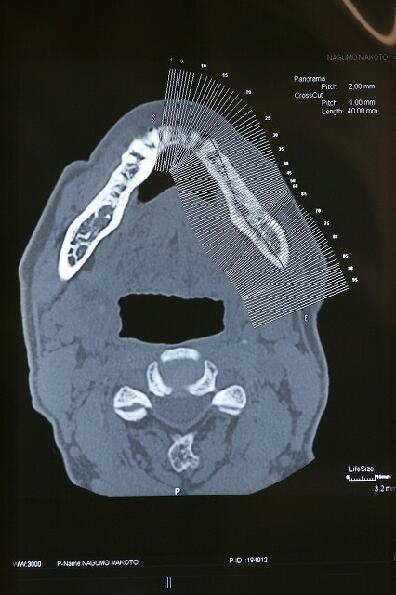

抜歯4ヶ月後のCTエックス線

輪切りにされた下顎骨

・真上の写真の楔状の切れ目はオトガイ神経の出口でインプラント埋入手術時は避けなければならない場所です

・このCTレントゲンによってインプラント埋入手術の安全性が大変高まっています

・このCTレントゲンを検討し、インプラント体(フィクスチャー)埋入場所、太さ等を決めていきます